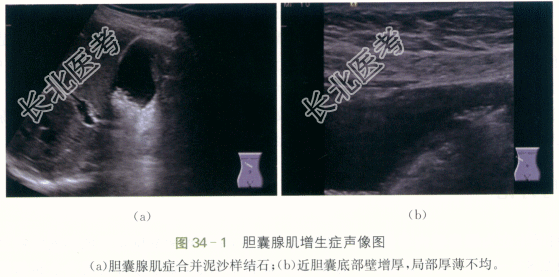

- [材料题] 患者,女性,47岁,因“反复右中上腹胀痛1月”就诊。伴厌油,食欲缺乏,不伴黄疸、胸痛、腹泻,无恶心呕吐,无反酸呃逆。大便正常,无黑便血便。既往有胆囊结石病史。体格检查:患者皮肤、巩膜无黄染,腹部平坦,未见明显胃肠型及异常隆起,全腹软,右上腹明显压痛,无反跳痛,右上腹未及包块,肝脾肋下未及,无肝肾区叩痛,Murphy征(-),肠鸣音正常。移动性浊音(-)。实验室检查:ALT39IU/L,AST28IU/L。影像资料如下: